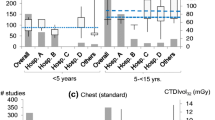

The DRLs for CTDIvol and DLP are determined for each patient size group as a function of water-equivalent diameter as follows: (I) < 13 cm (n = 22; median: age 7 months): 0.4 mGy, 7 mGy·cm; (II) 13 cm to less than 17 cm (n = 151; median: age 3 y): 1.2 mGy, 25 mGy·cm; (III) 17 cm to less than 21 cm (n = 211; median: age 8 y): 1.7 mGy, 44 mGy·cm; (IV) 21 cm to less than 25 cm (n = 97; median: age 14 y): 3.0 mGy, 88 mGy·cm; (V) 25 cm to less than 29 cm (n = 42; median: age 14 y): 4.5 mGy, 135 mGy·cm; (VI) ≥ 29 cm (n = 15; median: age 14 y): 8.0 mGy, 241 mGy·cm. Compared with corresponding age and weight groups, our size-based DRLs for DLP are 54% to 71% lower than national and 23% to 85% lower than European DRLs.

We calculated achievable doses and DRLs for the six patient size groups (Table 4). Patient size groups were matched to equivalent age and weight groups reported for the national and European DRLs [1, 26]. Local size-based DRLs for CTDIvol were 54% to 74% lower than national DRLs (54% to 71% lower for DLP) and 16% to 75% lower than European DRLs (23% to 85% lower for DLP) for corresponding age and weight groups (Table 5). Local size-based achievable doses for CTDIvol were 72% to 87% lower than national DRLs (75% to 87% lower for DLP) and 50% to 88% lower than European DRLs (56% to 93% lower for DLP).